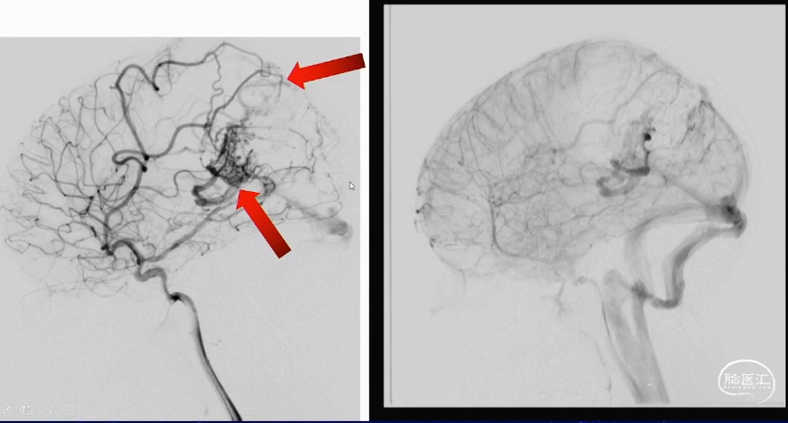

深浅引流:

经PCA栓塞主体部分:

只剩与引流V相连部分:

闭塞浅静脉及参与AVM:

闭塞深部引流V及残余AVM:

术后正侧位及3D:

术后6个月复查: